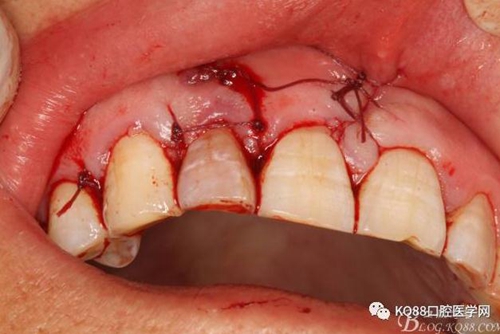

圖21.間斷縫合。